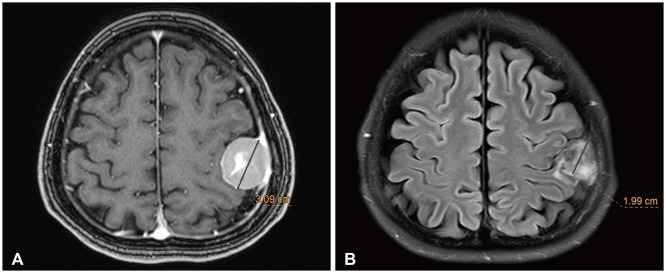

{"title":"Clinical Experiences Using CyberKnife for Large-Volume Meningiomas: A Preliminary Study.","authors":"Yonghun Song, Kyeong-O Go","doi":"10.14791/btrt.2024.0030","DOIUrl":null,"url":null,"abstract":"<p><strong>Background: </strong>This preliminary study evaluates the safety and efficacy of CyberKnife radiosurgery (CKRS) for large-volume meningiomas (≥10 cm³), where surgical options may be limited due to tumor location or patient health conditions.</p><p><strong>Methods: </strong>We retrospectively analyzed 18 patients with meningiomas treated with CKRS at Gyeongsang National University Hospital between 2010 and 2020. Tumor control and survival rates were evaluated, with follow-up imaging performed regularly.</p><p><strong>Results: </strong>CKRS achieved a 5-year overall survival rate of 92.3% and a 5-year tumor control rate of 93.8%. Symptomatic peritumoral edema occurred in 61.1% of patients, with 16.7% requiring surgical intervention.</p><p><strong>Conclusion: </strong>CKRS appears to be a promising option for patients with large meningiomas, showing good tumor control and manageable complications. Further studies with larger cohorts are necessary to confirm these findings.</p>","PeriodicalId":72453,"journal":{"name":"Brain tumor research and treatment","volume":"12 4","pages":"230-236"},"PeriodicalIF":0.0000,"publicationDate":"2024-10-01","publicationTypes":"Journal Article","fieldsOfStudy":null,"isOpenAccess":false,"openAccessPdf":"https://www.ncbi.nlm.nih.gov/pmc/articles/PMC11570087/pdf/","citationCount":"0","resultStr":null,"platform":"Semanticscholar","paperid":null,"PeriodicalName":"Brain tumor research and treatment","FirstCategoryId":"1085","ListUrlMain":"https://doi.org/10.14791/btrt.2024.0030","RegionNum":0,"RegionCategory":null,"ArticlePicture":[],"TitleCN":null,"AbstractTextCN":null,"PMCID":null,"EPubDate":"","PubModel":"","JCR":"","JCRName":"","Score":null,"Total":0}

Results: CKRS achieved a 5-year overall survival rate of 92.3% and a 5-year tumor control rate of 93.8%. Symptomatic peritumoral edema occurred in 61.1% of patients, with 16.7% requiring surgical intervention.